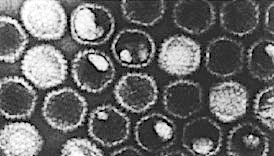

トリレオウイルス (ARV) はエンベロープをもたない二本鎖RNAウイルスです。世界中のニワトリや七面鳥から検出されており、ほとんどすべての商業用家禽群がこのウイルスのキャリアです。